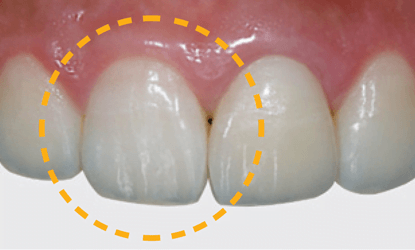

Vienmomentis funkcijos ir estetikos atstatymas

Laikinos restauracijos yra paruoštos atidavimui jau prieš operaciją. Šios restauracijos buvo sumodeliuotos CAD-CAM sistema, panaudojus PMMA ar kitas jums patinkančias medžiagas laikinų restauracijų gamybai.

Individualizuotos atramos ir karūnėlės

Vienmomentis priekinių dantų atstatymas laikinomis restauracijomis